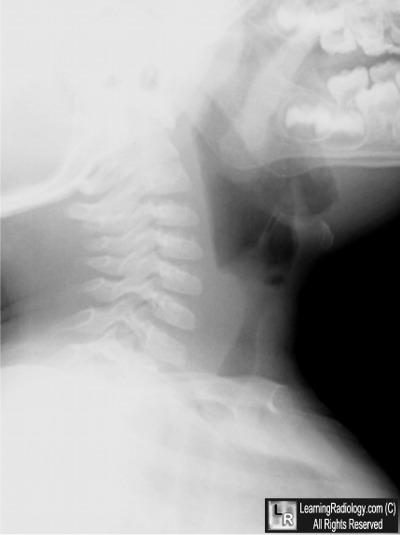

Soft Tissue Lateral Neck Radiograph

4. Croup

Croup

- Croup

- Laryngeotracheobronchitis

- Usually viral

- May be difficult to distinguish from early retropharyngeal abscess

- Occurs at age 6 months to 2 years

- Younger than epiglottitis

- The three major findings of croup

- Distension of the hypopharynx

- Distension of the laryngeal ventricle

- Haziness or narrowing of subglottic space